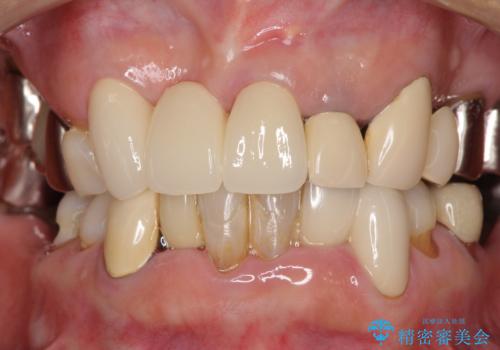

仮歯に置き換えた時点で見た目が大きく改善され、人目を気にすることがなくなりました。

オールセラミッククラウンは、仮歯以上に快適な舌触りや、本物の歯のような外観となり、患者様には大変満足していただけました。